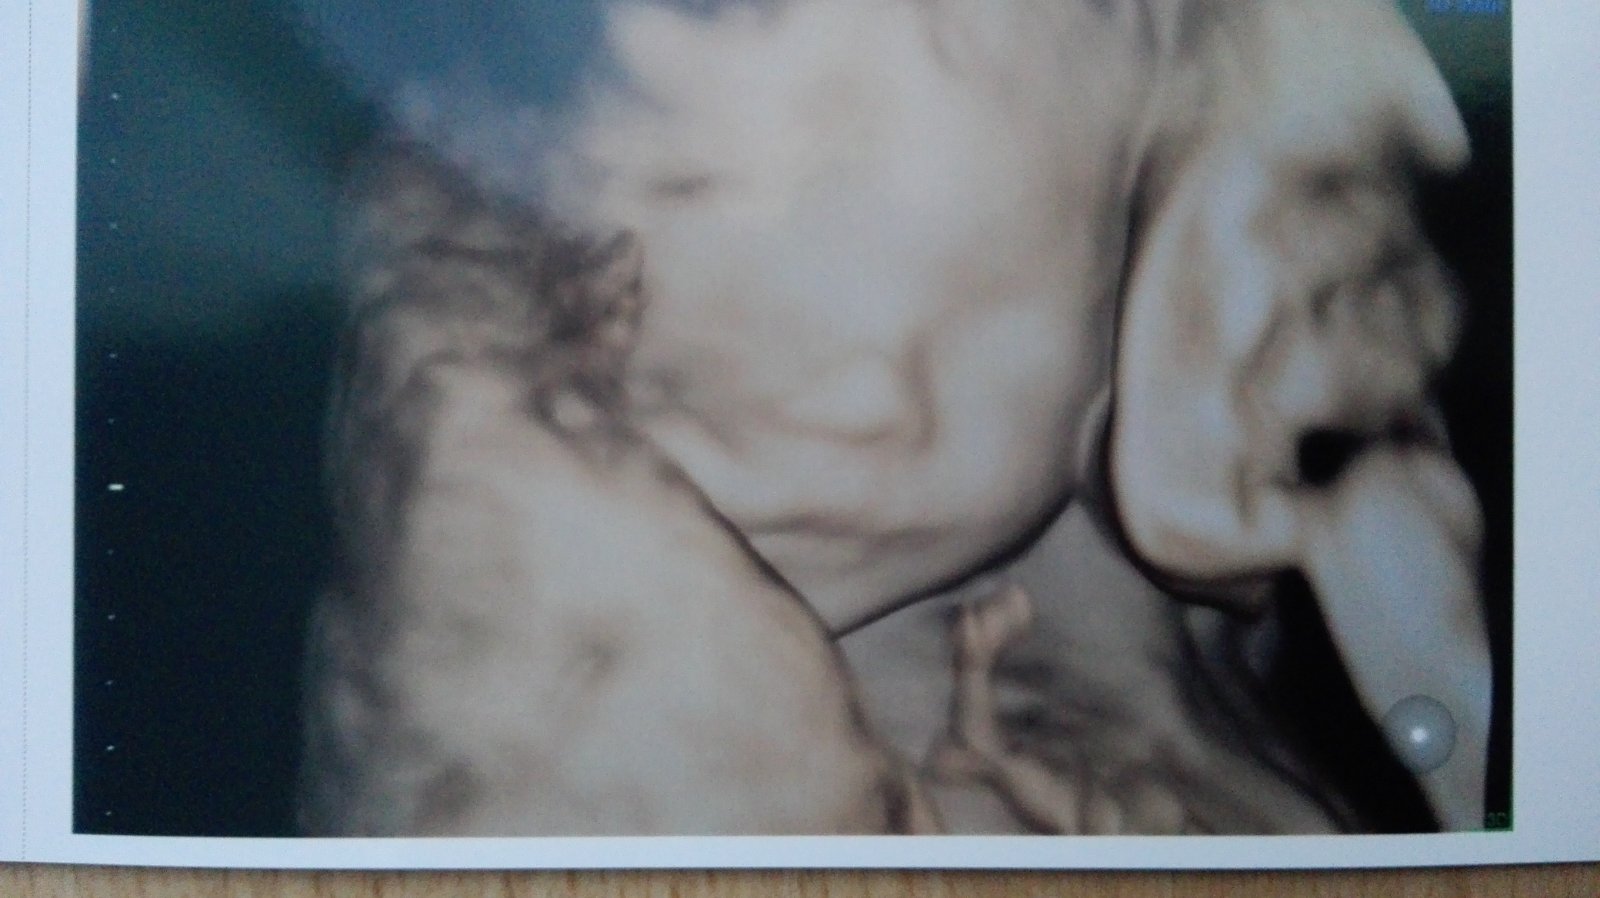

Ahojte, dnes som absolvovala sono u MUDr.Grochala a je všetko v poriadku, čakáme zdravého chlapčeka. Pán doktor povedal, že sa narodí buď veľký alebo skôr lebo podľa sona má už 458g a vyzerá to už na 22tt.

@martinsen Super krásny je,užívaj tehotenstvo